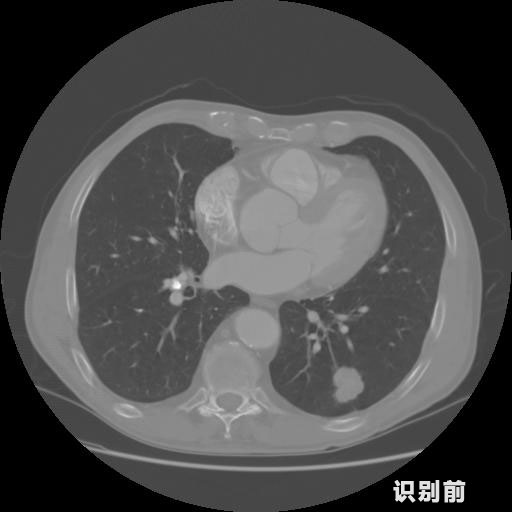

英特健康AI深度學習醫(yī)療圖像識別系統(tǒng)案例_胸部CT

1.發(fā)現肺結節(jié)的可能性為95.56%---位于框指數位置:[331.70554 366.13406 365.21707 403.96234]